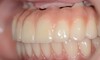

Aspect des deux bridges provisoires au bout de 6 mois. Des colorations sont apparues. La mandibule de la patiente est en retrait par rapport au maxillaire (classe2 squelettique).

Vue intra-orales des deux bridges. Noter les belles papilles au maxillaire antérieur et le retrait de la mandibule vers l’arrière corrigé par le montage des dents prothétiques.